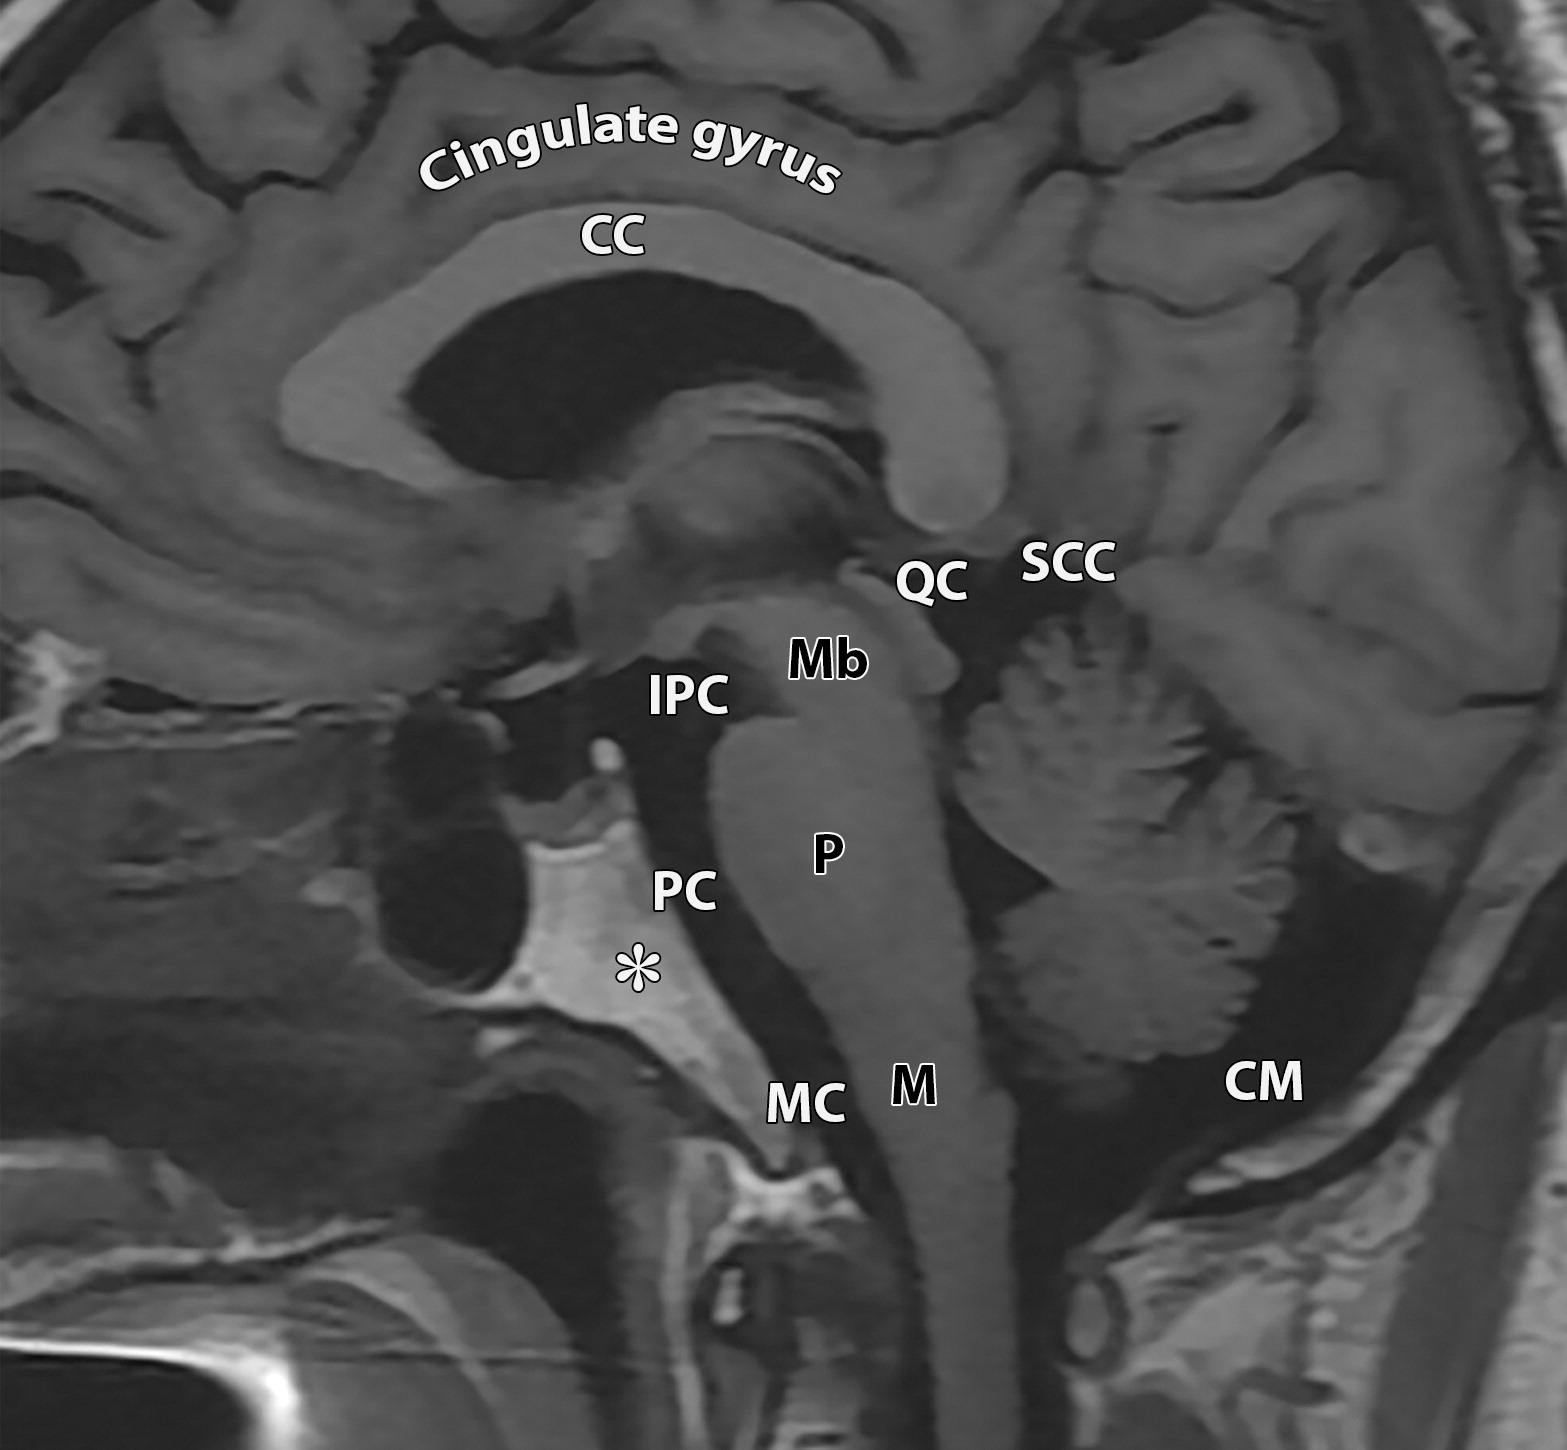

169690e0c66d9650f05be6cd7ce5d1fb.jpeg

枕大池(CM),脚间池(IPC),延髓池(MC),脑桥池(PC),四叠体池(QC),小脑上池(SCC),胼胝体(CC),扣带回(cingulate gyrus),斜坡(*),脑干组成:中脑(Mb),脑桥(P),延髓(M)。